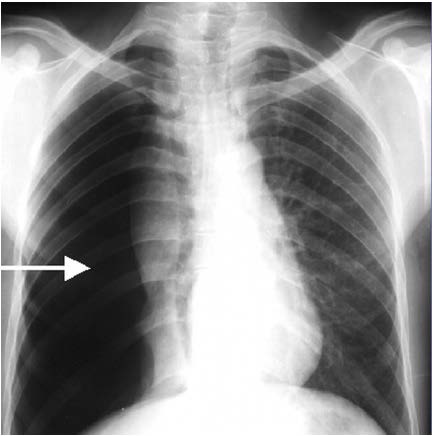

Ein wichtiger Warnhinweis (Frühsymptom), sei es über oder unter Wasser vor dem Auftreten von Luftnot, kann Reizhusten sein. Eine so beschriebene Atemwegsempfindlichkeit kann vorübergehend bestehen, wie zum Beispiel bei einer Bronchitis, oder sie besteht dauerhaft wie beim bereits angesprochenen Asthma bronchiale. Die Schwierigkeit bei der Ausübung des Tauchsports besteht für Asthmapatienten darin, dass das Risiko für eine Lungenüberdehnung (Barotrauma der Lunge = pulmonales Barotrauma) aufgrund von Air Trapping erhöht ist. Beim Air Trapping handelt es sich um die Situation, dass Luft während der Ausatmung durch die Verengung der kleinen Atemwege (Bronchiolen) nicht in dem Maße im Rahmen des Auftauchens (Dekompressionsphase) abgeatmet werden kann, wie sie eingeatmet wurde, und es daher zum Luftverhalt in diesen Lungenbereichen kommt. Daraus kann ein Lungenriss (mit folgendem Pneumothorax) in den entsprechenden Lungenbereichen resultieren (Abb. 1).

Abb. 1: Röntgenaufnahme des Brustkorbs. Frontalebene (a.p.-Aufnahme). Der weiße Pfeil markiert einen Lungen-leeren rechten Brustkorb (Patienten-rechts, links im Bild) in Folge eines Pneumothorax (Luft im Brustkorb). Hier zeigt sich kein Lungengewebe im Vergleich zur Gegenseite (Patienten-links, rechts im Bild). © Dr. Dr. Philipp Stahl

Eine Zusammenfassung zur COPD und Tauchsport gibt Info-Box III. Neben häufig bestehenden Komorbiditäten (Begleiterkrankungen) bei Patientinnen und Patienten mit COPD, wie Herz-Kreislauf- und Gefäßerkrankungen sowie Diabetes mellitus, welche die körperliche Leistungsfähigkeit und damit die Fähigkeit zur Erlangung einer Tauchtauglichkeit einschränken, bestehen erhebliche Gefahren beim Tauchen bei fortgeschrittenen Stadien dieser Lungenerkrankung. Hier ist vor allem die erhöhte Gefahr eines Pneumothorax (Lungenriss) zu nennen, der durch die überblähten Lungenbereiche (Lungenemphysem) in der Dekompressionsphase entstehen kann (Abb. 1). Prinzipiell ist der Pneumothorax auch bei nicht vorbestehendem Lungenemphysem bei der COPD analog zum Asthma bronchiale durch Air trapping und der dafür bereits aufgeführten Risikofaktoren möglich.